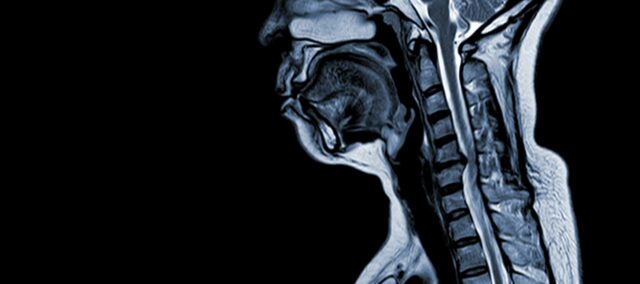

اعتلال النخاع الشوكي الفقاري العنقي (CSM) هو حالة عصبية تعد السبب الرئيسي لإصابة الحبل الشوكي لدى البالغين. بعبارات بسيطة، ينطوي على انضغاط أو تلف الحبل الشوكي في الرقبة، ويرجع ذلك في المقام الأول إلى عملية الشيخوخة الطبيعية التي تؤثر على الفقرات العنقية. ينبع مصطلح "اعتلال النخاع الشوكي" من الكلمتين اليونانية "myelon" التي تعني "النخاع الشوكي" و"باثوس" التي تعني "المرض".

يُعدّ التصلب الجانبي الضموري حالة طبية معقدة ذات فيزيولوجيا مرضية متعددة العوامل تتضمن تغيرات هيكلية في العمود الفقري العنقي. تساهم عدة عوامل رئيسية في تطوره وتطوره:

- تنكس القرص (انتفاخ القرص): وغالباً ما يبدأ التصلب العضلي النخاعي الشوكي المركزي بتنكس الأقراص الفقرية في العمود الفقري العنقي، مما يؤدي إلى انتفاخها أو بروزها في القناة الشوكية.

- تكوين العظم تحت السمحاق (بطني إلى القناة الشوكية): واستجابة لزيادة الضغط الميكانيكي، يقوم الجسم بتشكيل نسيج عظمي جديد على الجانب الأمامي (البطني) من القناة الشوكية، مما قد يؤدي إلى تضييق المساحة المخصصة للحبل الشوكي.

- تعظم الرباط الطولي الخلفي الخلفي: قد يخضع الرباط الطولي الخلفي الخلفي للتعظم والتصلب والتكلس، مما يساهم في تضييق القناة الشوكية.

- تضخم الأربطة الفلافية: يؤدي تضخم الأربطة الفلافية إلى زيادة سماكتها وتصبح أقل مرونة، مما يزيد من التعدي على المساحة داخل القناة الشوكية ويضغط على الحبل الشوكي.

وتؤدي هذه التغيرات الهيكلية مجتمعة إلى انضغاط القناة الشوكية وتضييقها، مما يؤدي إلى ظهور الأعراض والمضاعفات المميزة المرتبطة بالتصلب المتعدد الكيسات. ويُعد التعرف على عوامل الخطر هذه وفهم الآليات الفيزيولوجية المرضية المعنية أمرًا ضروريًا للوقاية من المرض وإدارته. يعد التشخيص المبكر والتدخلات المناسبة أمرًا بالغ الأهمية للتخفيف من آثار هذه التغيرات الهيكلية على الحبل الشوكي.